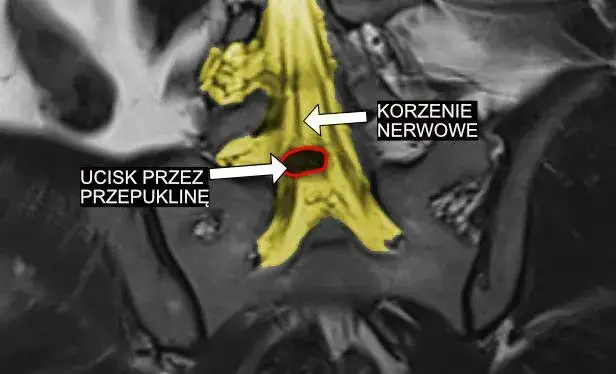

W diagnostyce zaburzeń korzeni nerwowych i splotów nerwowych stosuje się różne metody, które pozwalają na dokładne zbadanie stanu pacjenta. Rezonans magnetyczny (MRI) to jedno z najczęściej używanych badań, które dostarcza szczegółowych obrazów struktur wewnętrznych ciała, pomagając w identyfikacji uszkodzeń nerwów. Elektromiografia (EMG) to kolejna ważna metoda, która ocenia aktywność elektryczną mięśni i może ujawnić problemy z przewodnictwem nerwowym. Tomografia komputerowa (CT) również jest wykorzystywana, zwłaszcza gdy konieczne jest uzyskanie przekrojowych obrazów ciała. Dzięki tym badaniom lekarze mogą lepiej zrozumieć, jakie dokładnie zaburzenia występują i jak je skutecznie leczyć.

Interwencja chirurgiczna staje się konieczna, gdy metody zachowawcze nie przynoszą oczekiwanych efektów lub gdy występują poważne uszkodzenia nerwów. Wskazania do operacji mogą obejmować ciężkie bóle, które nie ustępują mimo leczenia farmakologicznego, oraz objawy neurologiczne, takie jak osłabienie mięśni czy utrata czucia. Typowe procedury chirurgiczne to odbarczenie nerwów, które polega na usunięciu ucisku na nerwy, oraz stabilizacja kręgosłupa, która ma na celu przywrócenie prawidłowej struktury kręgosłupa. W każdym przypadku decyzja o operacji powinna być dokładnie przemyślana i omówiona z lekarzem specjalistą.